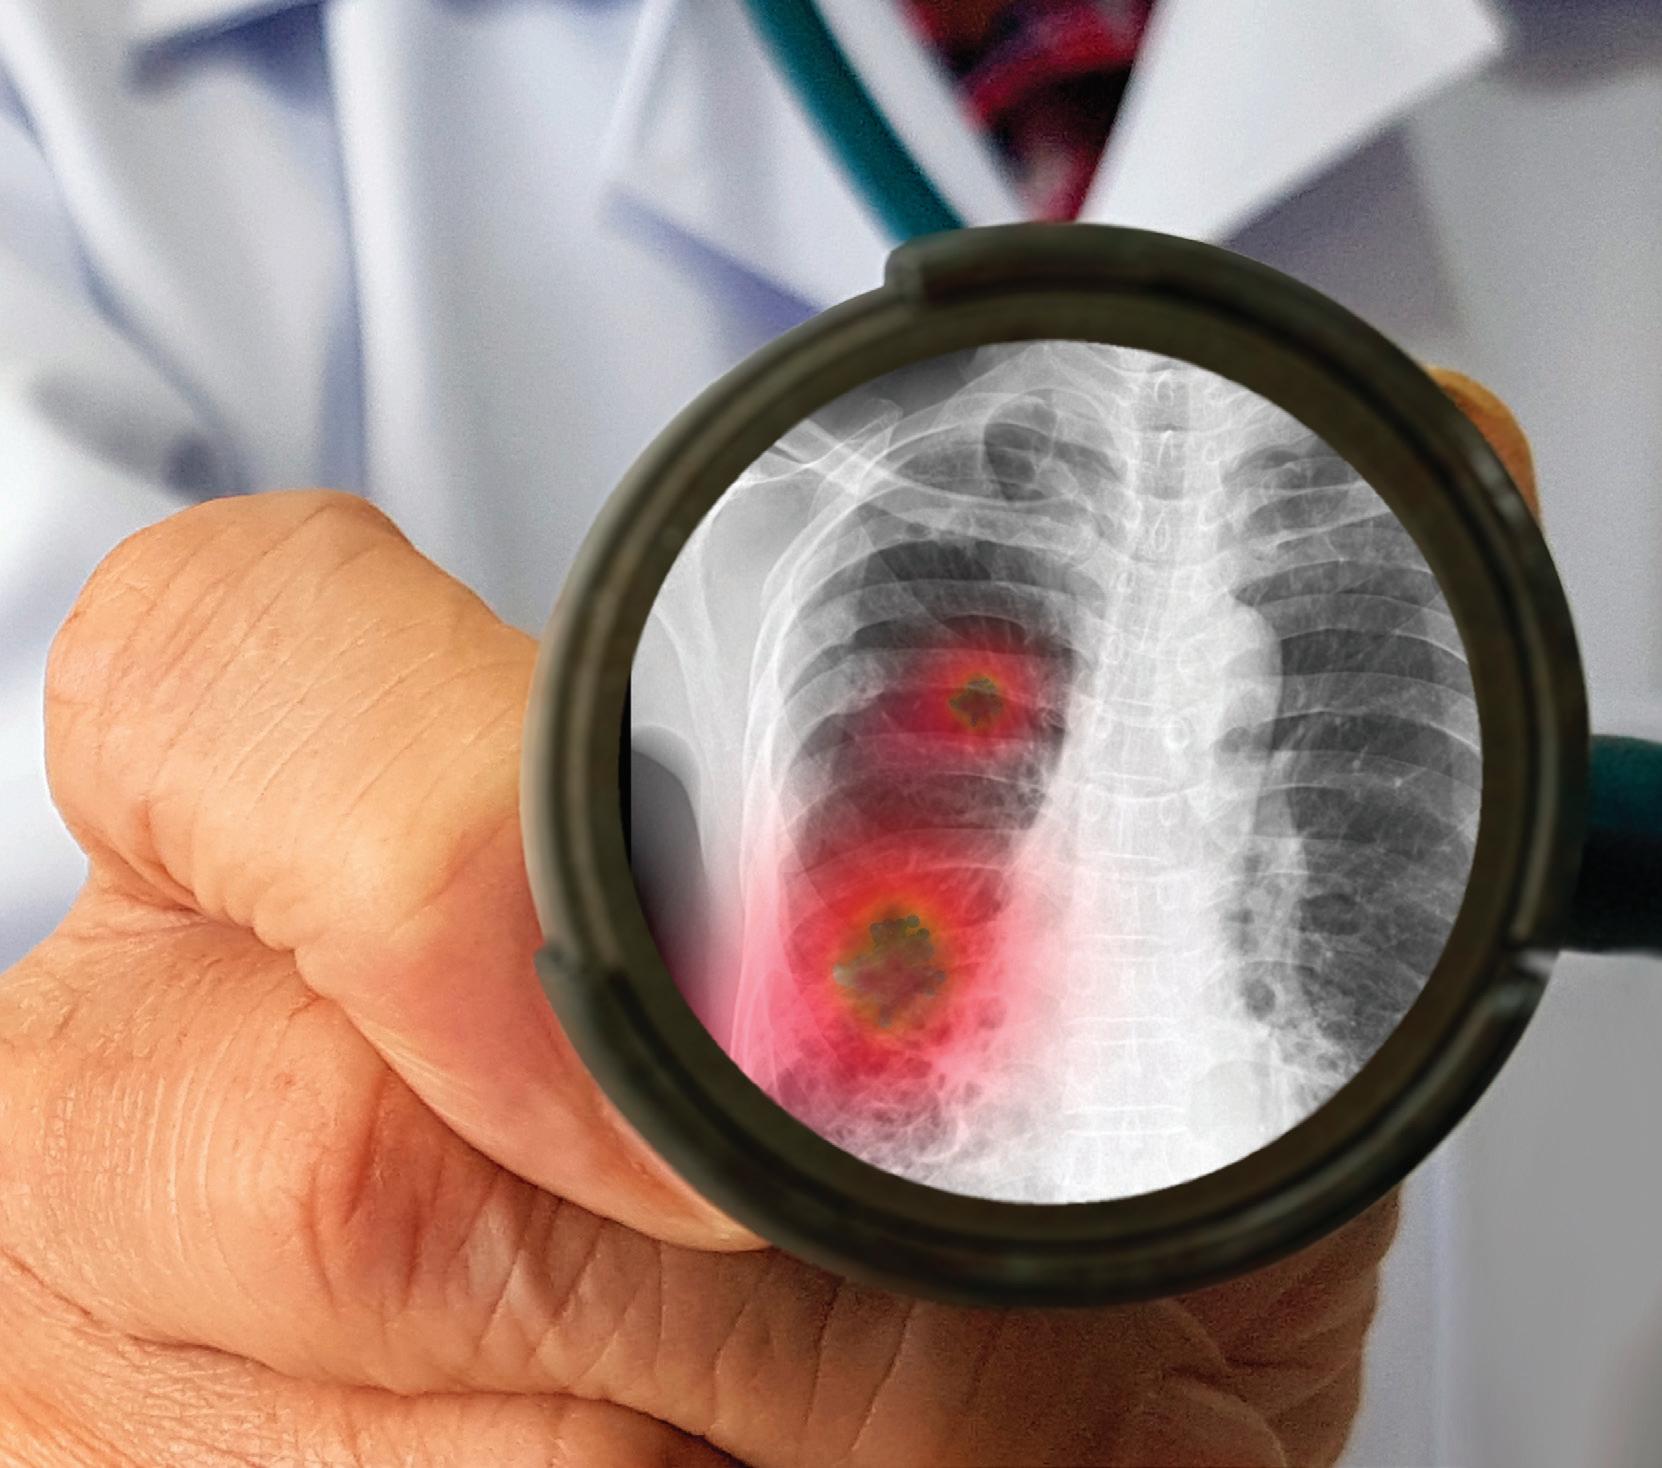

П. Павлов Медицински Университет - Плевен

Пневмонии, придобити в обществото – съвременни

решения в клиничната практика

Ключови думи: Пневмонии, тенденции, поведение.

Пневмонията е едно от най-големите открития на клиничната медицина. Диагнозата и лечението й в днешно време се усложняват от появата на нови, непознати патогени, разширяващата се антибиотична резистентност, увеличаващата се популация на имунокомпрометирани пациенти, модерни диагностични методи и антимикробни средства.